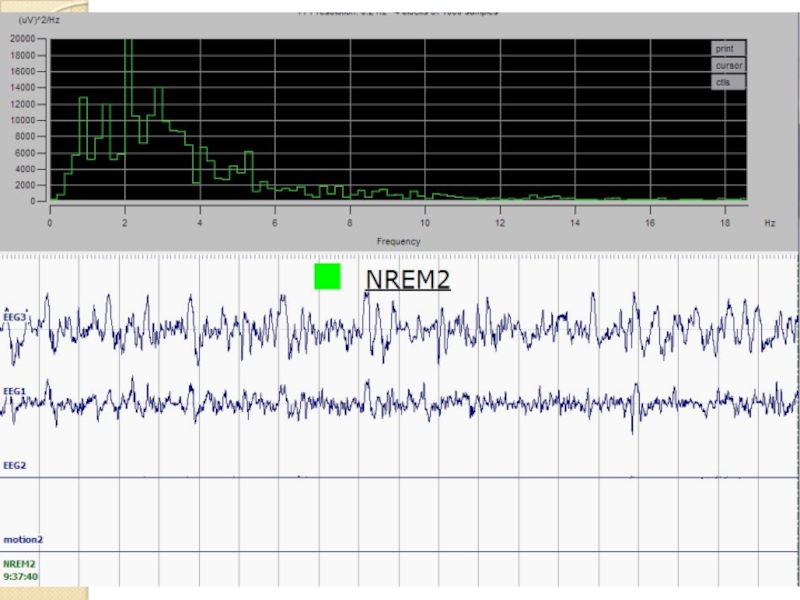

- 12. Стадирование сна по ЭЭГ Примеры записей ЭЭГ и движения Бодрствование Медленный сон Быстрый сон